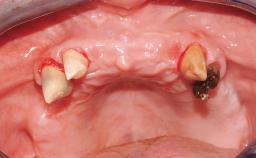

A 63-year-old male patient was referred for a consultation and treatment of partial edentulism in the maxilla. The patient presented with residual anterior teeth and declined a partial removable prosthesis. He reported that the maxillary posterior teeth had been extracted due to mobility and periodontal disease two months before the consultation. The patient’s chief complaint was that his residual maxillary teeth were mobile and that he was unable to chew. The patient’s desire was a stable and comfortable fixed maxillary rehabilitation. The patient was a light smoker (fewer than 10 cigarettes/ day), and his medical history was without significant findings. He was not on any regular medication at the time of consultation. The extraoral examination revealed a normal physiognomy with a correct distribution of the facial thirds. The patient presented a low lip line, and the transition line between teeth and soft tissues was not exposed during a forced smile.

Bone Augmentation Horizontal|Simultaneous

Augmentation Materials Xenogenous

Bone Volume Horizontally and vertically sufficient